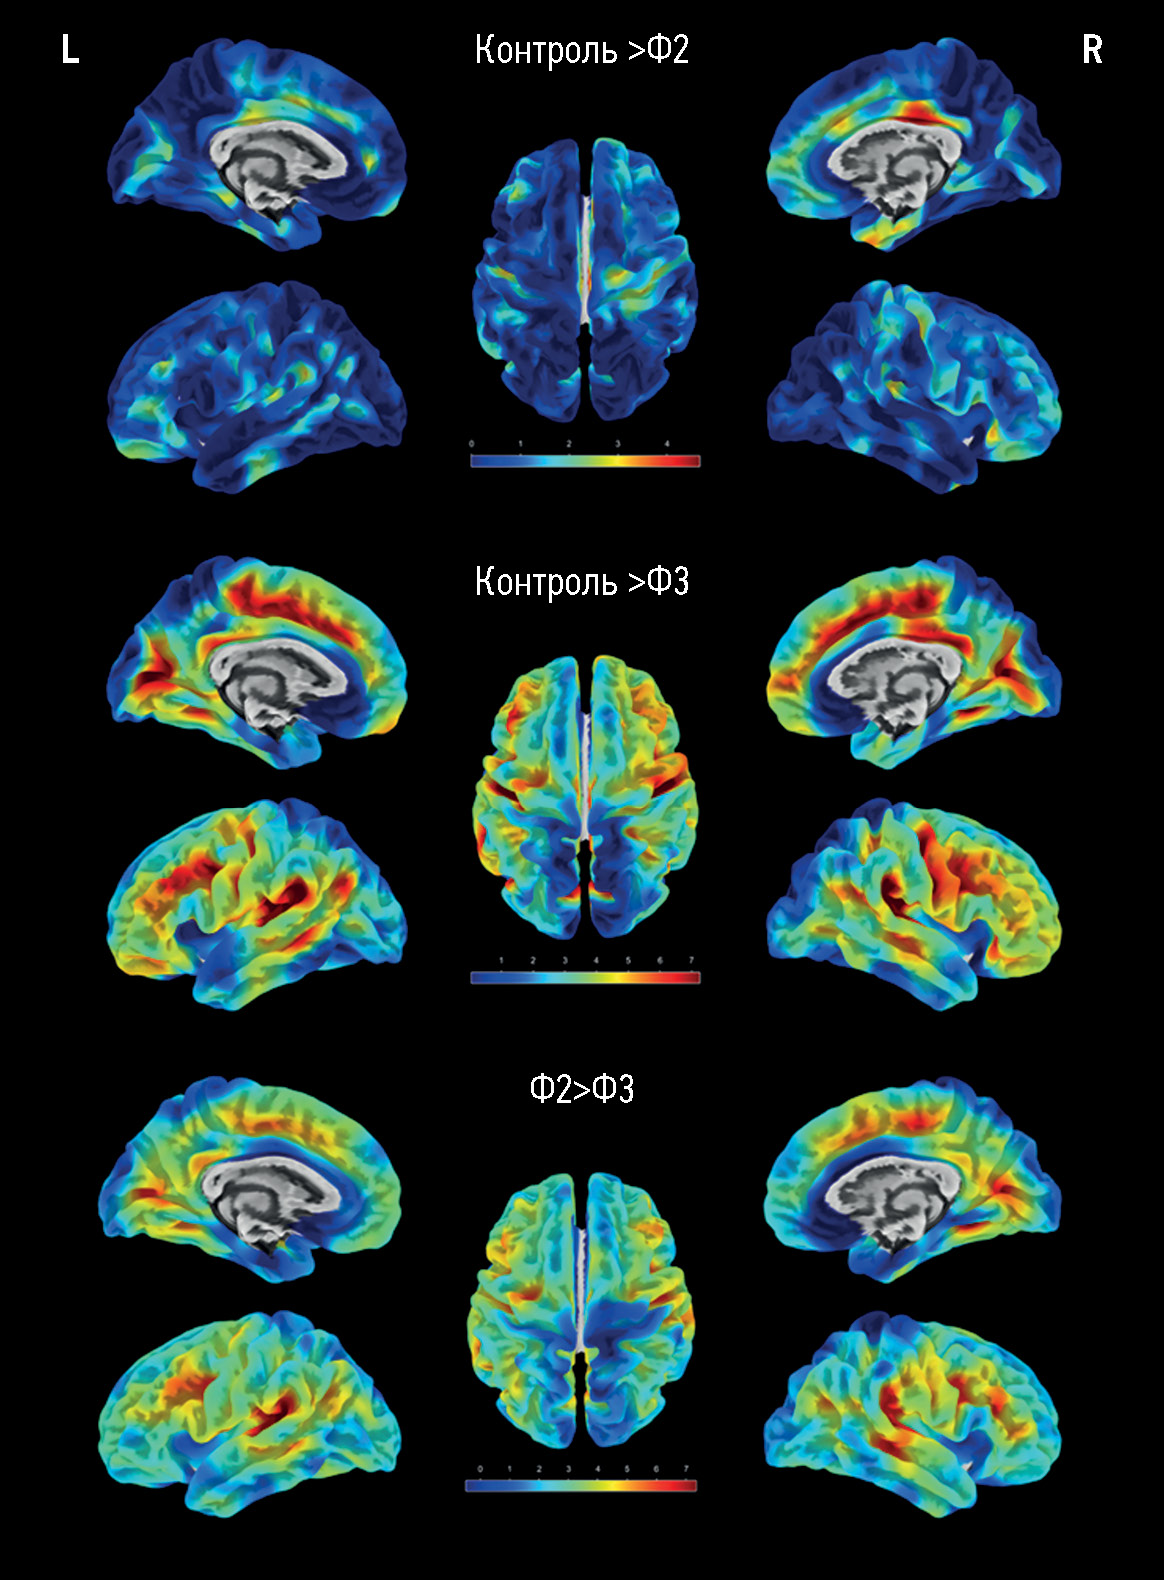

RESULTS: The main group consisted of 173 patients with cerebral small vessel disease, whereas the control group included 47 healthy volunteers. As the severity of brain structural changes and cognitive impairments increased, a significant (p <0.05) decrease in the cortical thickness of certain regions following a similar pattern was reported, particularly in the cingulate gyri, mainly their posterior sections; medial and middle sections of the frontal lobes, various areas of the insular cortex, and temporoparietal areas, particularly the supramarginal gyri. The brain volumes (overall, gray matter, and white matter volumes) in cerebral small vessel disease were significantly different only in controls but not between patients with cognitive impairment of different severity levels. The hyperintense white matter volume was significantly different between patients with dementia and moderate cognitive impairment, dementia, and subjective cognitive impairment (p <0.0001).

CONCLUSIONS: The results confirm secondary/mixed atrophy in cerebral small vessel disease. The clarification of the severity level of cognitive impairment in cerebral small vessel disease based on atrophy data is limited by the wide variety of regions with significant cortical thinning. Thus, the quantification of the cortex can only be a supplementary method in predicting cerebral small vessel disease progression.